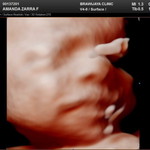

Pertumbuhan janin terhambat

Bunda Kemarin saya usg dan dokter spog nya bilang bb janin tertinggal 2 minggu Sedih banget Disini ada yg pertumbuhan janin nya terhambat juga gak ya ? Sharing yuk bund